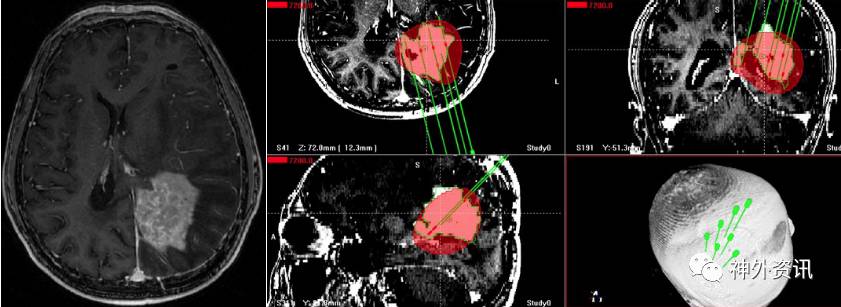

完善术前准备,并经过科室讨论后,于2016.8.16行立体定向125I粒子植入术,术前复查头颅MRI增强,提示激素使用后,肿瘤未见明显缩小。根据放射性粒子植入计划系统(TPS)系统,设计7个穿刺道,共计植入34颗125I粒子(图5)。

图5. MRI检查肿瘤未见明显缩小。TPS系统设计7个穿刺道。